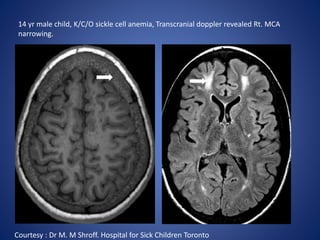

14 yr male child, K/C/O sickle cell anemia, Transcranial doppler revealed Rt. MCA

narrowing.

Courtesy : Dr M. M Shroff. Hospital for Sick Children Toronto

14 yr malechild, K/C/O sickle cell anemia, Transcranial doppler revealed Rt. MCA narrowing. Courtesy : Dr M. M Shroff. Hospital for Sick Children Toronto